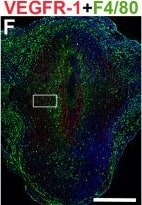

VEGFR-1, CD31, F4/80, and CD11b expression in the pre-implantation mouse uterus. IHC and double staining IF were performed on E3.5 uterine cross-sections. (A) Schematic representation of an E3.5 mouse uterus showing lumen (arrowheads), glands, stroma (s), and myometrium (myo). (B) ECs, detected by CD31 staining (brown), are observed throughout the stroma and myometrium, similar to the non-pregnant state. (C) Macrophages, detected by F4/80 staining (brown), are observed throughout the stroma and are abundant adjacent to the lumen and glands at E3.5. (D) VEGFR-1+ cells (brown), are distributed throughout the stroma and cell associated VEGFR-1 expression highlighted in the inset. (E) Double staining for VEGFR-1 (red) and CD31 (green) demonstrates expression of VEGFR-1 on CD31+ ECs throughout the stroma. (F) VEGFR-1+ cells (red) and F4/80+ macrophages (green) are distributed throughout the stroma. VEGFR-1 and F4/80 co-expression is not observed. (G) VEGFR-1+ cells (red) and CD11b+ monocytes (green) are distributed throughout the stroma. VEGFR-1 and CD11b co-expression is not observed. L, lumen. Scale bars B, C = 100 μm. Scale bars D – F = 50 μm. Image collected and cropped by CiteAb from the following publication (https://pubmed.ncbi.nlm.nih.gov/25101167), licensed under a CC-BY license. Not internally tested by R&D Systems.